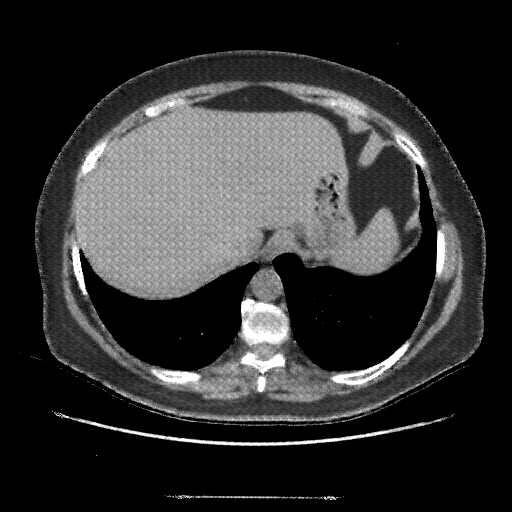

Original VENOUS CT scan

Full window (WL 1023.5, WW 4095 β†’ Low βˆ’1024, High +3071)